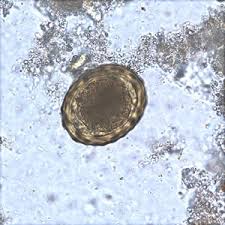

trichuris trichiura jaja